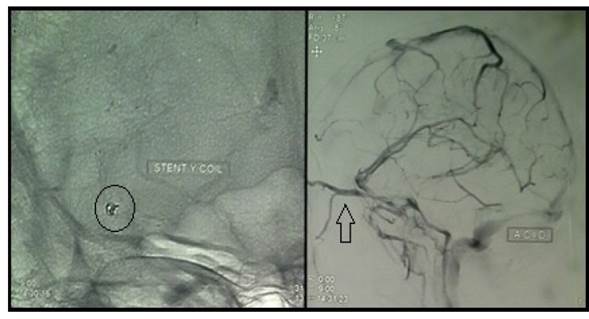

Una vez realizado el diagnóstico de HSA por aneurisma (CIE-10: I60), localizado en la arteria temporal anterior derecha, se procedió al tratamiento endovascular con endoprótesis vascular y microespirales asociado a doble tratamiento antiplaquetario con aspirina, 100 mg/día y clopidogrel, 75 mg/día. Se utilizó una endoprótesis vascular tipo Lvis Jr de 3,5 mm x 23 mm (LVIS® Jr. Intraluminal Support 3,5 mm / 23 mm - MicroVention, Inc) previa antiagregación, además de microespirales (3D Detachable Coil 2 mm x 2 cm AxiumTM) entre las arterias cerebral media y temporal anterior derecha para obliterar el aneurisma y mantener permeable la circulación cerebral (figura 2). El procedimiento se realizó con la paciente bajo anestesia general con rocuronio 30 mg + fentanilo 200 μg + propofol 50 mg, y duró 2:30 horas. Durante el procedimiento la paciente no presentó ninguna complicación.